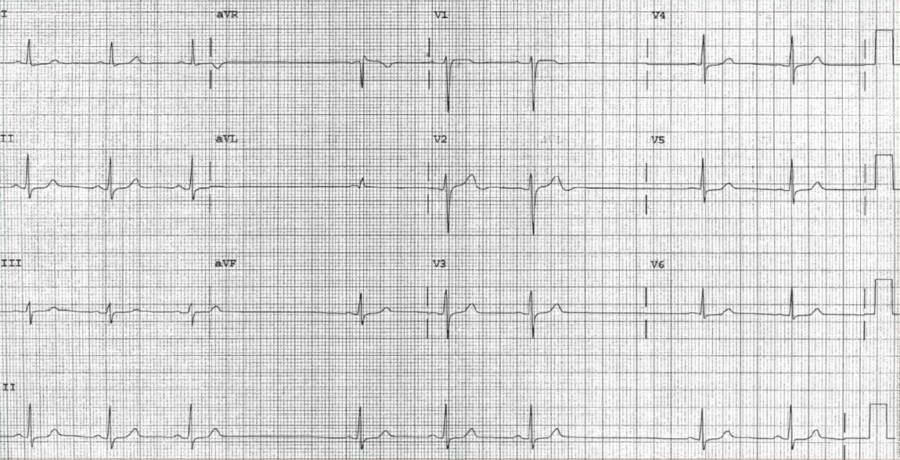

A 62-year-old man with an extensive history of smoking and a recent diagnosis of squamous cell carcinoma of the neck that was treated with radiation now presents with 2 weeks of intermittent dizzy spells and one episode of syncope.

You obtain the following ECG while performing carotid massage, which provokes the patient’s symptoms.

What’s your interpretation ?